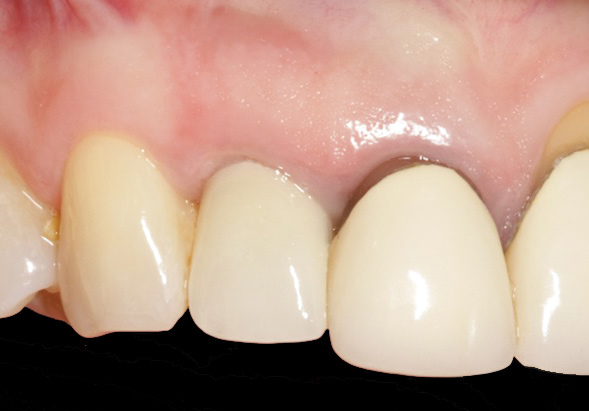

Fig 2. Radiograph showing implant was placed too deep and the diameter of the implant may be slightly larger than what was needed.

Figure 2

Caneva et al also suggested placing implants in a lingual (eg, cingulum) position to achieve optimal esthetic outcomes. The authors assessed the effect of implant positioning on resorptive patterns of the alveolar bone crest and demonstrated the importance of placing implants in a lingual position to minimize buccal bone resorption and thus prevent exposure of the implant. In their study, an average of 0.6 mm more buccal bone resorption was seen on implants that were placed in the center of the socket when healing after 4 months was compared histologically with implants that were positioned toward the lingual bony wall.17 In addition, placing a wider-diameter cylindrical implant in the extraction socket with the aim of filling the void between the implant and the inner socket wall was also shown to present greater buccal alveolar bone resorption (Figure 2).18,19 Based on these findings, it has been suggested that implant placement be performed in the palatal position of the socket to allow the formation of a gap between the implant surface and the inner buccal bone wall surface.19 More recently, in a retrospective cohort study, Cosyn and coworkers evaluated 115 patients who underwent implant placement with function. At 31 months, the buccal shoulder position of the implant was significantly associated with an increased likelihood of midfacial recession.3

When placing an implant in the esthetic zone, ideal 3-dimensional positioning, including mesio-distal, apico-coronal, and orofacial dimensions, is essential to achieve favorable esthetic outcomes, regardless of the implant system used (Figure 6).45 With respect to the orofacial dimension, implants should be placed in a more palatal or lingual position to allow the presence of at least 2 mm of buccal bone thickness from the implant buccal shoulder.45,46 When the distance of the buccal bone wall and implant buccal shoulder is < 2 mm, a significantly higher incidence of midfacial recession has been previously reported.3,12 Placement of bone graft (Figure 7) and immediate restoration (Figure 8 and Figure 9) at the time of implant placement has also been suggested to increase peri-implant soft-tissue height and thickness.51 In the apico-coronal dimension, the implant head should be at least 3 mm apical to an imaginary line connecting the CEJ of the adjacent teeth and 1 mm to 2 mm apical to the interproximal and crestal bone to ensure a proper implant emergence profile and facilitate proper implant restoration (Figure 10). Regarding the horizontal implant–tooth distance, implants should be placed no closer than 1.5 mm from the adjacent root surface to minimize resorption of the interproximal alveolar crest, which causes a reduction in the papillary height.46,52